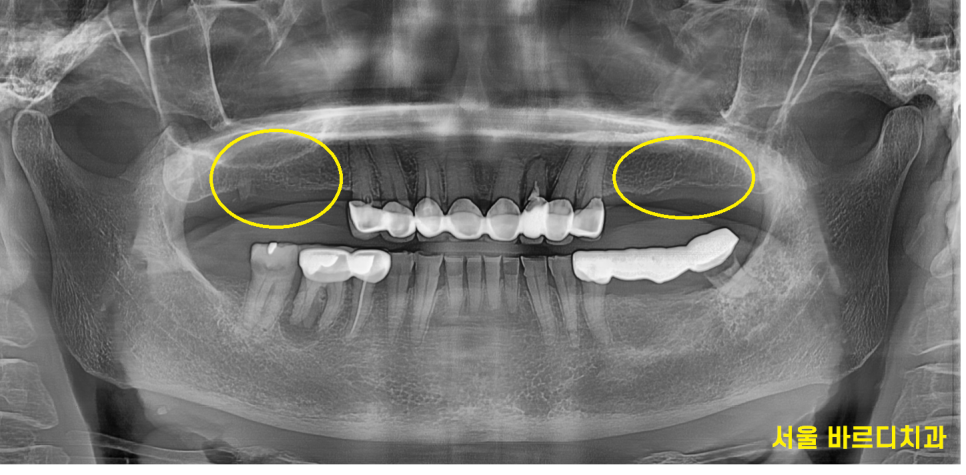

처음 오셨을때 윗니 어금니 6개가 빠져있었는데요.

양쪽 작은 어금니 1개로 식사를 하고 계셨습니다.

230526

오른쪽 위에 어금니는 치아가 없고

아래 어금니의 경우 염증으로 잇몸 뼈가 녹아있었는데요.